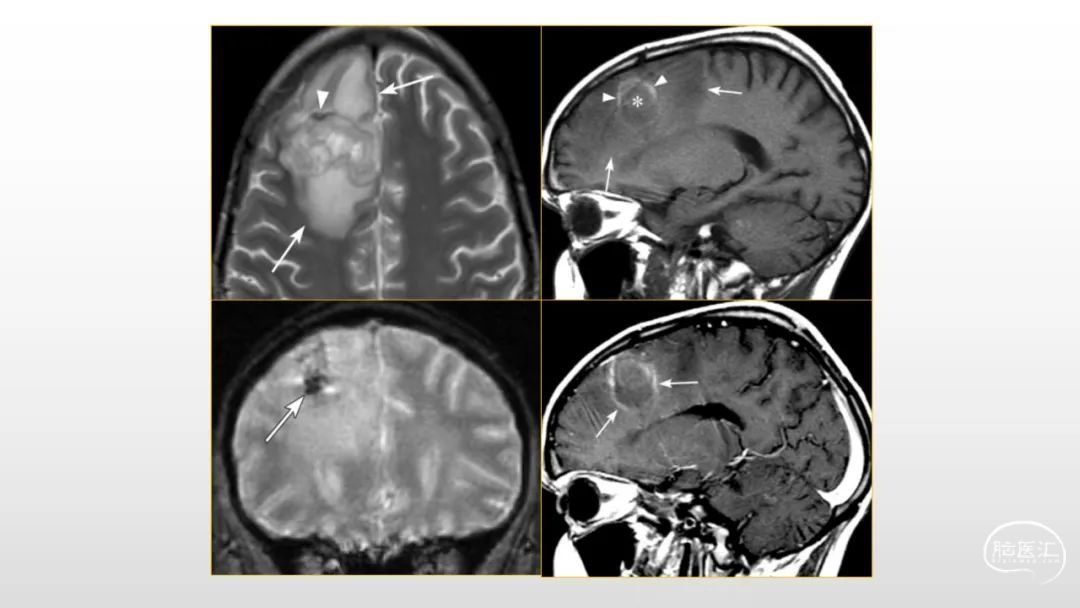

颅脑影像诊断基础知识讲座:感染和免疫性疾病1